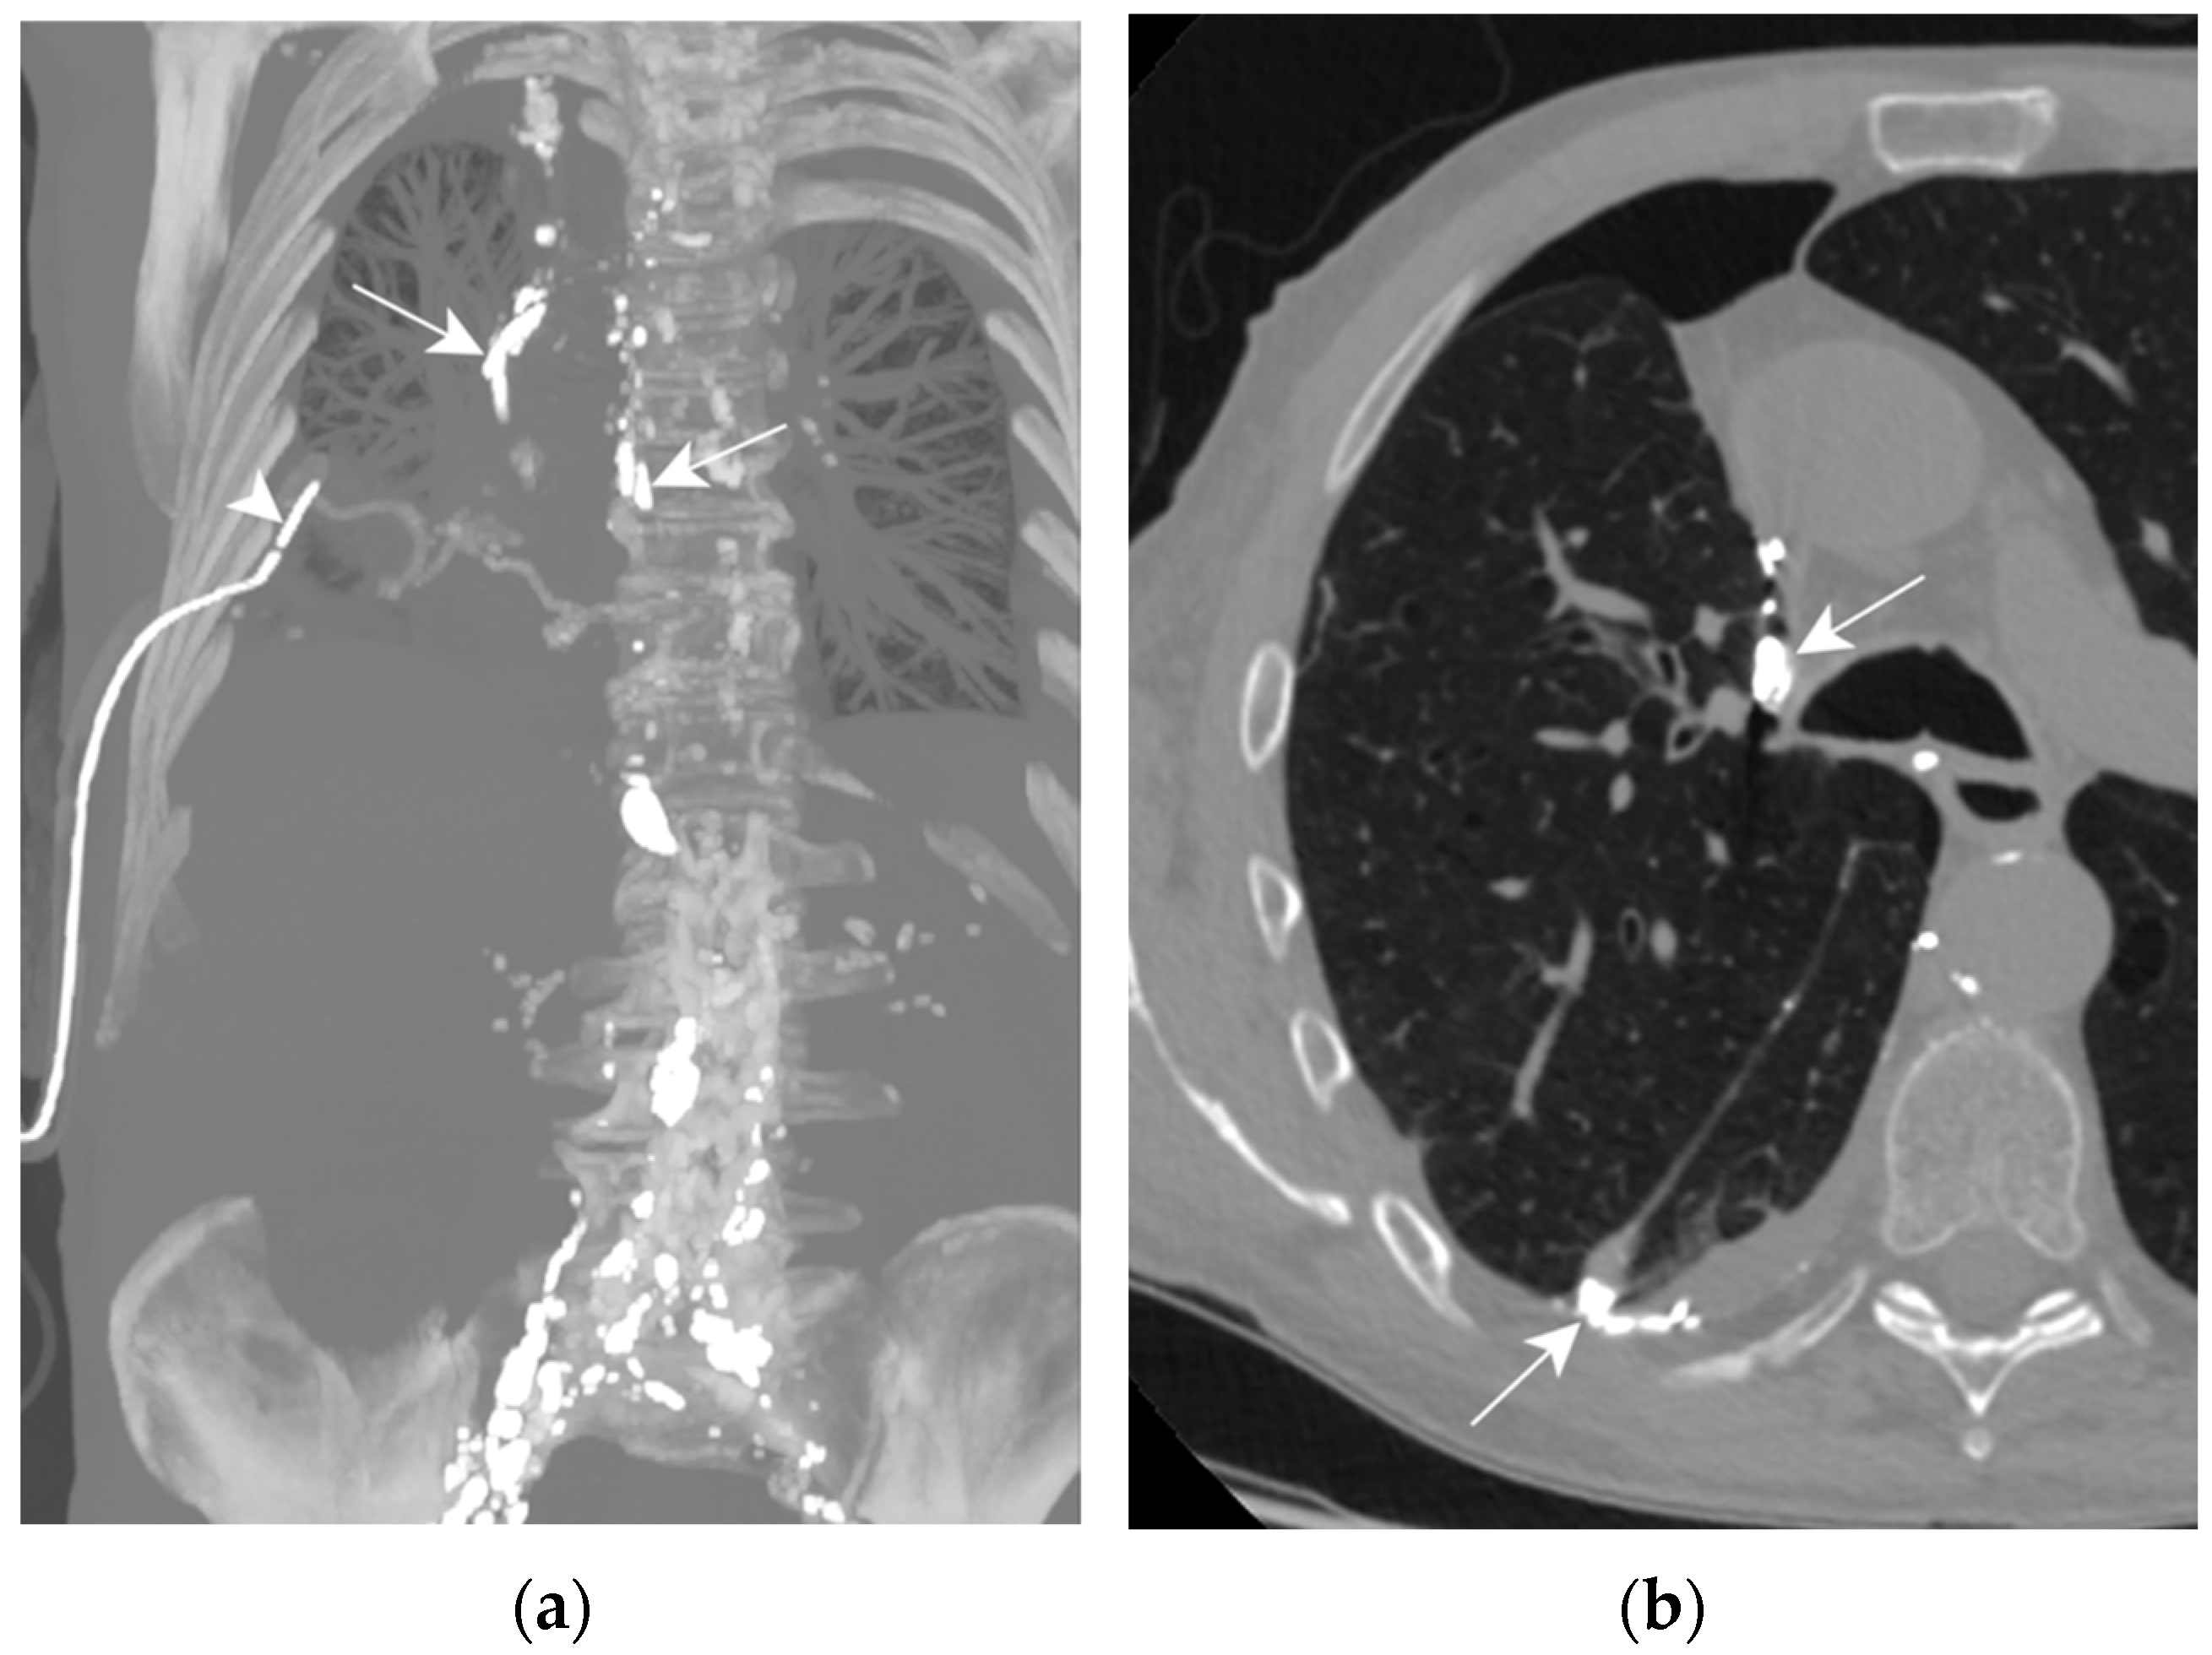

A right sided, high-output chylothorax (>900 mL/d) was diagnosed on post-operative day 1, TPN was immediately begun. Ten days after TPN, drain output was still high leading to surgical revision. A re-thoracotomy with ductus thoracicus ligation was attempted, but unsuccessful. An LL was then attempted to identify the location of the leak. Lymphography was technically successful, showing images of extravasation from the mediastinal lymph nodes in the right pleural space (Figure 7a,b). The reason for the persistence of chylothorax was a bilateral thoracic duct.

Figure 7.

Patient C. The maximal-intensity projection of the CT scan reconstructed in the coronal plane (a) and the axial CT plane through the upper pulmonary lobes (b). (a,b) Accumulation of hyperattenuating Lipiodol in an encapsulated collection in the apical portion of the right pleural space (black asterisks). The ductus thoracicus is dilatated (white arrow). Two right pleural catheters are shown (white arrowheads).

This intervention enabled drain output to be reduced by half but did not succeed in sealing the leak. The problem was finally solved by a VATS left sided thoracic duct ligation. This case was previously described by Rouiller et al. in 2020 [41].